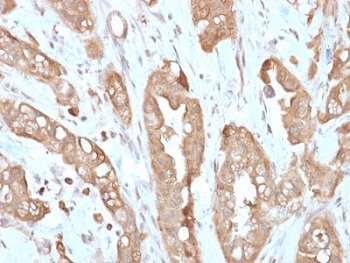

Villin Antibody. Immunohistochemistry analysis of Villin-1 (VIL1) in FFPE human small intestine using Villin Antibody / Epithelial Polarity Marker Antibody with recombinant rabbit monoclonal clone VIL1/2310R. Strong HRP-DAB brown staining is observed along the apical membrane of intestinal epithelial cells, clearly outlining lumen-facing surfaces and emphasizing apical-basal polarity within glandular structures. The predominantly apical membranous pattern highlights organized epithelial polarity and intact lumen formation, consistent with Villin localization as a polarity-defining cytoskeletal protein in absorptive epithelium.

Villin-1 (VIL1) is a calcium-regulated actin-binding protein that localizes specifically to the apical domain of epithelial cells, where it serves as a key regulator of apical-basal polarity and lumen formation. Villin Antibody / Epithelial Polarity Marker Antibody (clone VIL1/2310R) is designed to detect this polarity-defining protein, and Villin antibody, also known as Villin-1 antibody or VIL1 antibody, is widely used to study epithelial organization and directional cell architecture. As an epithelial polarity marker, Villin is tightly restricted to the lumen-facing membrane, making it a reliable indicator of polarized epithelial structure in tissues such as the intestine and glandular epithelium.

Epithelial polarity requires the establishment of distinct apical and basolateral compartments, and Villin plays a direct structural role in defining the apical domain through regulation of actin filament organization. By controlling actin bundling, severing, and capping at the apical surface, Villin supports the formation of a stable luminal interface and contributes to the development of organized epithelial layers. Researchers using a Villin Antibody / Epithelial Polarity Marker Antibody are typically focused on understanding how cells establish polarity, form lumens, and maintain directional organization within tissues. This polarity-driven positioning clearly differentiates this antibody from other Villin pages centered on brush border structure or general cytoskeletal function.

In polarized epithelial systems, Villin produces a distinct apical staining pattern that directly corresponds to lumen formation and maintenance. Proper localization of Villin is associated with intact epithelial architecture, while mislocalization or loss of apical restriction can indicate polarity defects, disrupted lumen formation, or tumor-associated dedifferentiation. These features make Villin a valuable marker in studies of epithelial morphogenesis, cancer progression, and tissue remodeling, where polarity is a key biological readout. Villin Antibody / Epithelial Polarity Marker Antibody is therefore particularly useful in identifying polarized versus non-polarized cell populations and assessing structural organization at the cellular level.